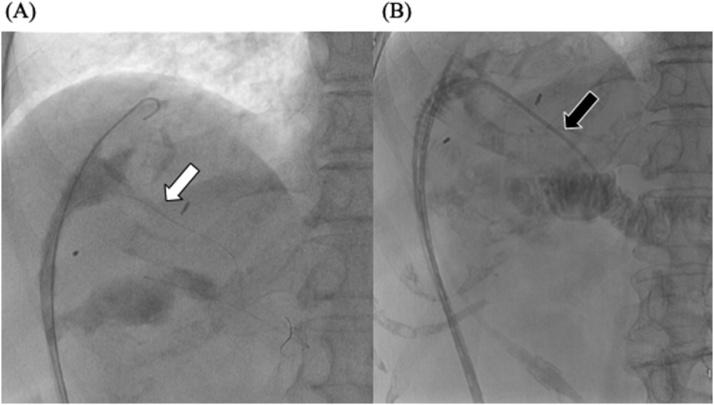

一名80岁女性,有远端胆管癌胰十二指肠切除术及辅助化疗史,出现胆漏。胰十二指肠切除术后6年,她因怀疑转移或肝内胆管癌接受了部分肝切除术。术后第9天,胆汁从引流管漏出,形成脓肿腔;这种情况一直持续到术后第28天。我们尝试在透视引导下,使用导丝和眼镜蛇型导管从肝脏切面进行选择性顺行引流。我们选择性地将胆管入口插管。引流20天后,脓肿腔消失。41天后,拔除引流管,患者出院。我们建议将此操作作为处理困难胆漏病例的一种可能的治疗选择。